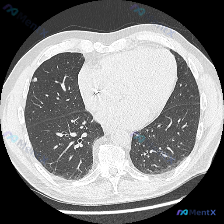

看到一份胸部CT肺窗的影像资料,整理了一下分析思路,和大家交流讨论。 病例资料 影像类型:胸部CT肺窗横断面图像 主诉:仅提供影像学资料,无临床症状及病史信息 影像学分析 解剖结构观察 - 肺实质:右肺上叶可见一枚类圆形高密度结节影,边界相对清晰,周围肺组织未见明显渗出或实变。双肺肺野透亮度均匀,无...